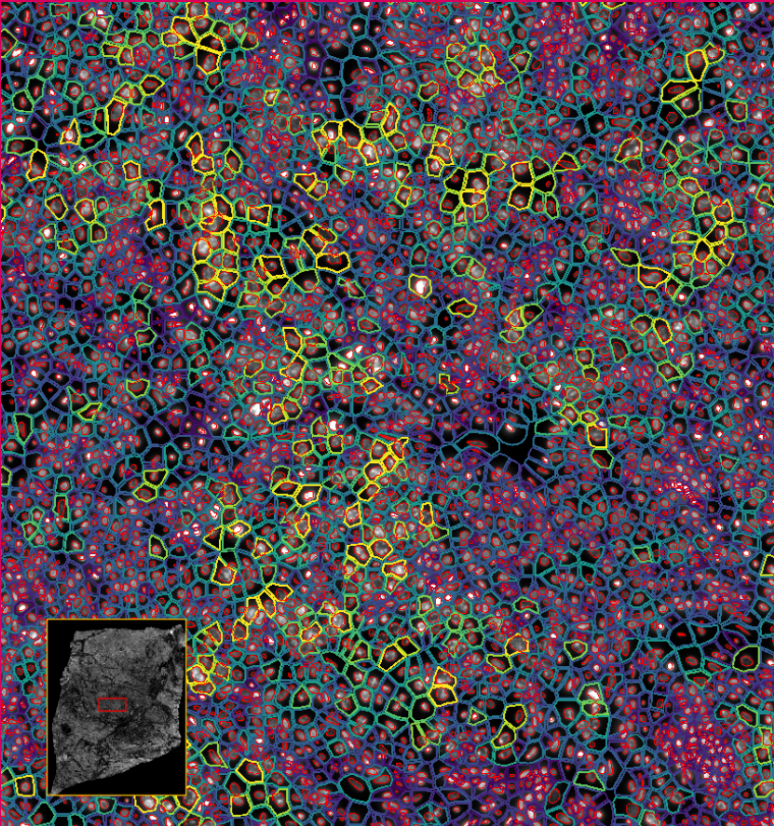

image.png

ͼ1£ºÖ×Áö²¡Àí±ê×¢

ͼ3£ºXenium½«¹âÑ§ÌØÕ÷½âÂëΪת¼±¾±í´ï£¬£¬£¬£¬£¬ÊÕÂÞ²¢ÐγÉͼÏñ